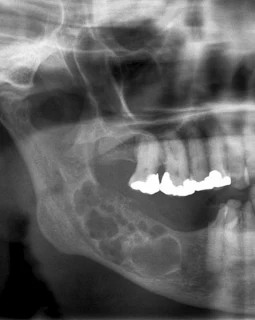

Dişlerin mine içeriğini salgılayan uzun, prizmatik, çok sayıda mitokondriyon, iyi gelişmiş Golgi organı ve granüllü endoplazma retikulumunu içeren koruyucu işlevli hücre, enameloblastus. Ameloblastlar dişin çiğneme yüzeyini meydana getiren en sert dış katman olan diş minesini oluşturan hücrelerdir.

Ameloblastlar, insan vücudundaki en sert madde olan diş minesini oluşturmak için daha sonra mineralize olacak olan mine proteimleri enomelin ve amelogenini salgılayan hücrelerdir.

Vücudun en sert ve en yoğun mineralleşmiş maddesidir.